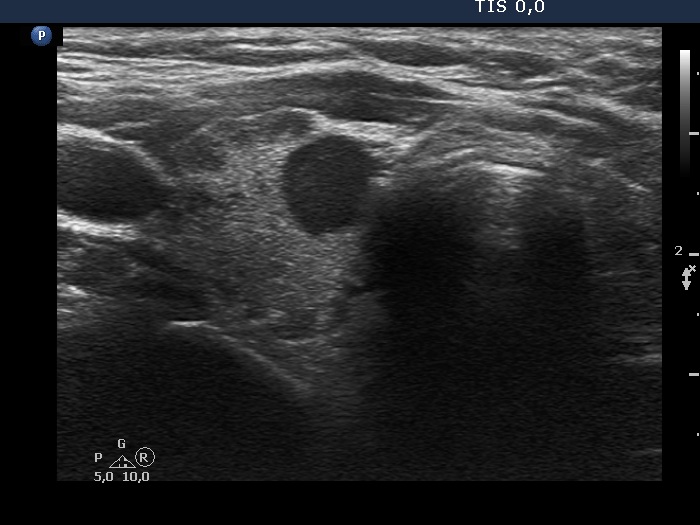

Clinical data: A 54-year-old woman was referred for evaluation of a nodule. She has been treated for hypothyroidism for seven years.

Ultrasound. The thyroid had numerous moderately hypoechoic fields corresponding to the underlying thyroiditis. The echogenicity index exceeded 50%. There was a hypoechoic nodule in the right lobe. The shape was close to consider nonparallel, but the largest width exceeded the largest depth. The nodule showed irregularities at the border. On the degree of these irregularities, the possibility of irregular borders can be raised. The intranodular vascularization was extremely increased.

Cytology was performed form the hypoechoic nodule and resulted in Hashimoto's thyroiditis.

- Nonparallel orientation is defined as the largest depth to exceed the largest width or length, taller-than-wide or taller-than-long shape, respectively. Although in certain sections the depth exceeded the widht, bit this was not true if we related the largest depth to the largest width. Therefore, the nodule did not present nonparallel orientation.

- It is equivocal whther the borders should be considered as irregular or should not.